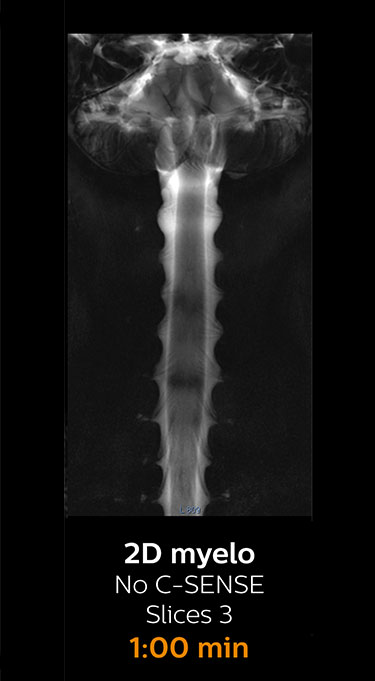

With Compressed SENSE, the scan time for the routine cervical spine examination at KNC was reduced from 13:11 to 9:52 minutes, which corresponds to 25% reduction.

MRI examination of the cervical spine with Compressed SENSE

Ingenia 3.0T CX

Scan time 9:52 min. (was 13:11 min. without Compressed SENSE)